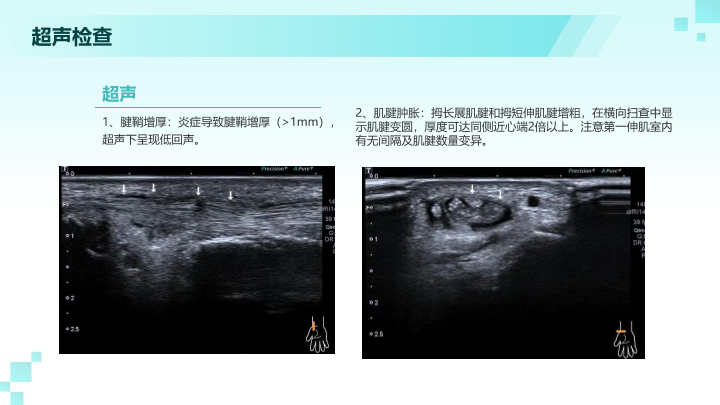

妈妈手桡骨茎突腱鞘炎